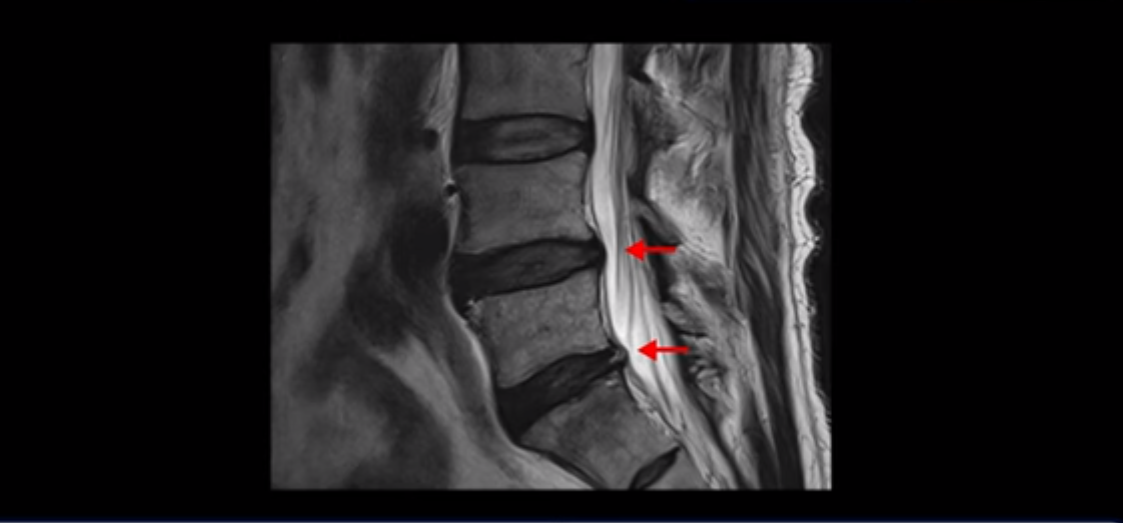

먼저 이분 MRI를 보면서 간단히 설명해 드린 후 어떻게 신경이 눌려서 수술해야 한다는 환자를 수술 없이 치료할 수 있는지, 또 어떤 병원에서는 수술할 정도로 심하지는 않다고 했는데 왜 증상은 이렇게 심한지, 그러면 수술 없이 치료는 어떻게 할 수 있는 건지 자세히 설명해 드리겠습니다.

이분 허리 MRI를 보면 60세가 넘었기 때문에 퇴행이 진행은 되었지만 아주 심하지는 않습니다.

이분 왼쪽 다리가 저리고 아파서 2~3년 전부터 걷기가 힘들었는데 이분 허리 4번, 5번 마디에 신경 가지가 빠져나가는 추간공이 다른 마디에 비해서 좁아져 있습니다. 하지만 아주 심하게 좁아져 있지는 않습니다.

의사마다 MRI를 보고 얘기가 달랐다고 하는데 심하지 않다고 하는 쪽이 맞습니다. 그런데 이분은 신경 구멍 넓이에 비해 증상은 매우 심한 편입니다. 왜 그럴까요? 이 이유와 어떻게 치료하는지에 대해 지금부터 설명해 드립니다.